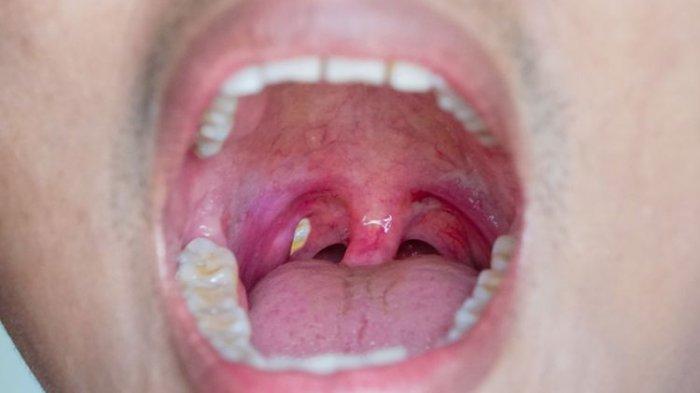

Dengan begitu bisa diketahui anomali-anomali yang terjadi di dalam rongga mulut mulai dari adanya abses, sariawan hingga gangguan lainnya.

Dokter Gigi, drg. R. Ngt. Anastasia Ririen Pramudyawati menambahkan jika terjadinya abses merupakan bagian dari proses peradangan.

Dalam peradangan selalu ada perubahan warna menjadi lebih memerah karena suplai darah banyak menuju ke area tersebut untuk bisa menangani atau menyembuhkan secara alami proses peradangan yang sedang berlangsung.

Selain itu juga akan terjadi perubahan bentuk atau terjadi pembengkakan.

"Umumnya secara fisik abses gigi bisa dilihat dan diamati apakah terdapat pembengkakan," sambung Dokter Gigi, drg. R. Ngt. Anastasia Ririen Pramudyawati.

"Apabila disentuh akan terasa lunak atau konsistensinya lunak," lanjut Dokter Gigi, drg. R. Ngt. Anastasia Ririen Pramudyawati.

"Hal ini apabila kondisi infeksi atau pembengkakan sudah tembus hingga area jaringan lunak," tambah Dokter Gigi, drg. R. Ngt. Anastasia Ririen Pramudyawati dalam tayangan Sapa Dokter (21/01/2022).

Dokter Gigi, drg. R. Ngt. Anastasia Ririen Pramudyawati menambahkan jika pada beberapa kasus dimana pernanahannya masih di dalam tulang, pasien bisa tidak melihatnya atau tidak bisa mendeteksinya secara fisik.